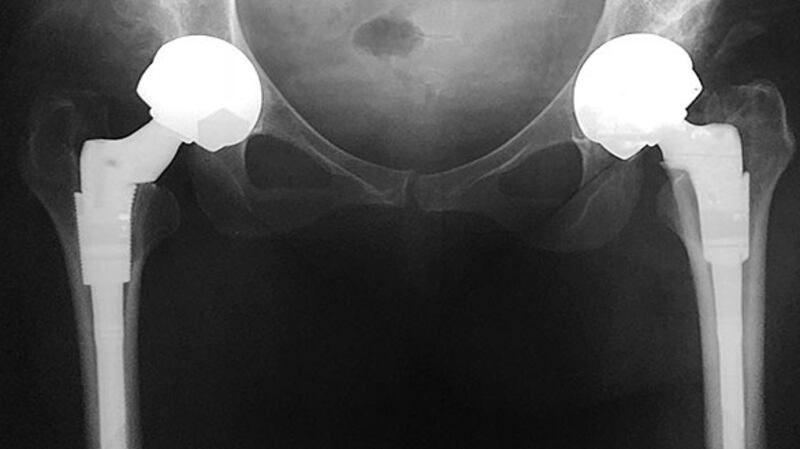

When Gillian O'Sullivan gets up from her chair to fetch some hip X-rays, you can't but notice that one of her legs is shorter than the other.

Her surgeon was referring to a new metal product from DePuy, a subsidiary of Johnson & Johnson and a major manufacturer of orthopaedic products. The so-called ASR hip came in two variants. One was a hip resurfacing device, which covered the cup and ball of the hip socket, while the second was a total hip replacement product, which involved replacing the top of the femur with a metal device, which then sat into the metal cup.

Both products differed from what was previously on the market in that both traditional hip implants used a metal ball and a polyethylene or plastic cup. The DePuy hip had a ball and cup made out of a hard-wearing cobalt chromium metal alloy.

In October 2005, Gillian O’Sullivan had a DePuy hip replacement device implanted on her left side at the Kilcreene Orthopaedic Hospital in Kilkenny. In May 2006, her second hip was replaced.